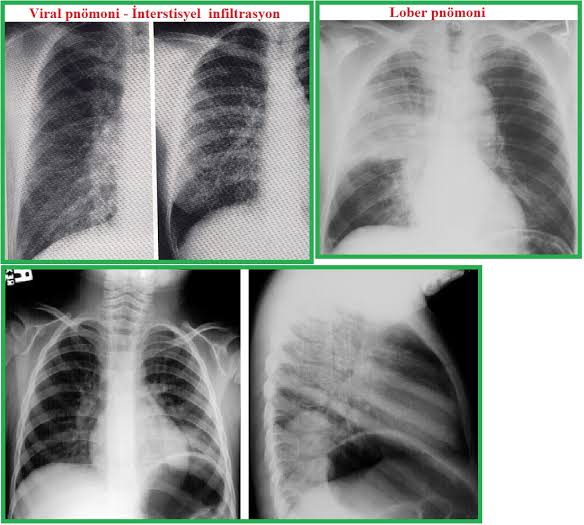

Zatürre çeşitleri:

1)Bakteriyel Pnömoni: Etken ajanlar bakterilerdir.

2)Viral Pnömoni: Genellikle ağır gripten sonra görülür. Virüsler üst solunum yolu mukozasına yapışır ve zamanla akciğerlere iner. Genellikle yaşlılarda; diyabet, astım ve kalp hastalığı gibi kronik hastalığı olanlarda; beslenme bozukluğu olan ve bağışıklık direnci küçük kişilerde ağır grip sonrası zatürre’ye çevirir.